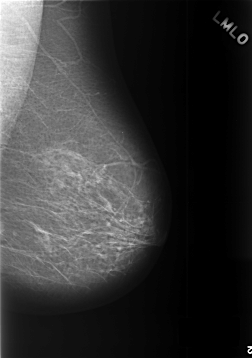

C_0392_1.LEFT_MLO

C_0392_1.LEFT_CC

LEFT_MLO LINES 5728 PIXELS_PER_LINE 4024 BITS_PER_PIXEL 12 RESOLUTION 50 NON_OVERLAY